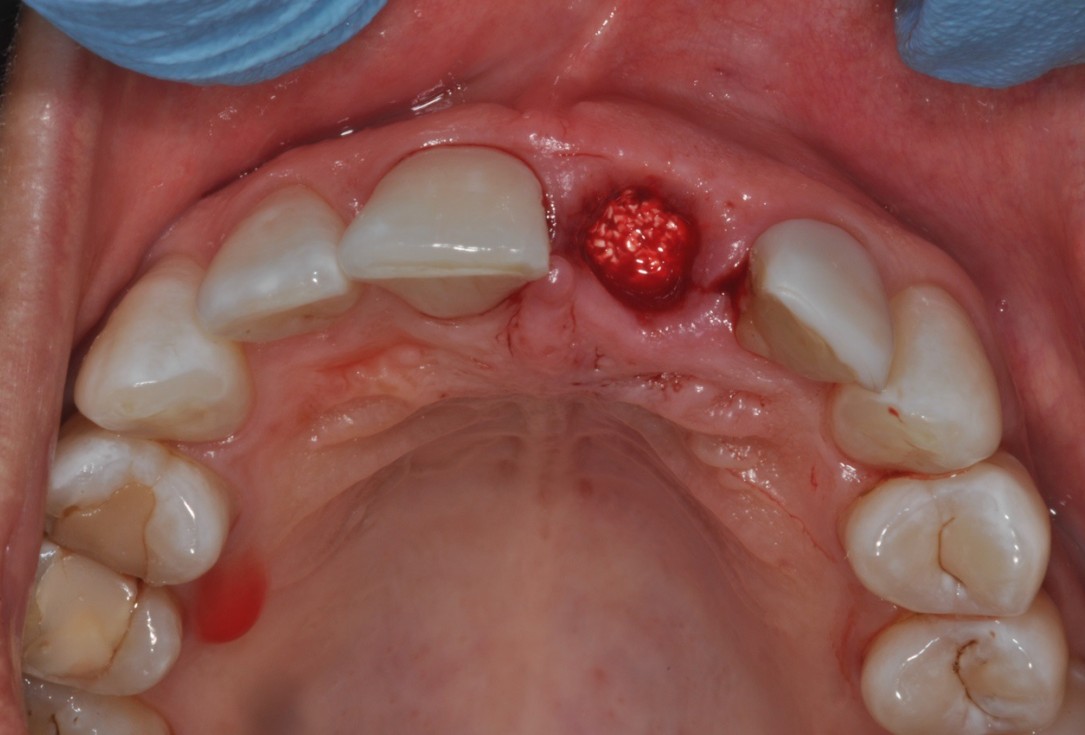

04/16 - Extraction of tooth root 21